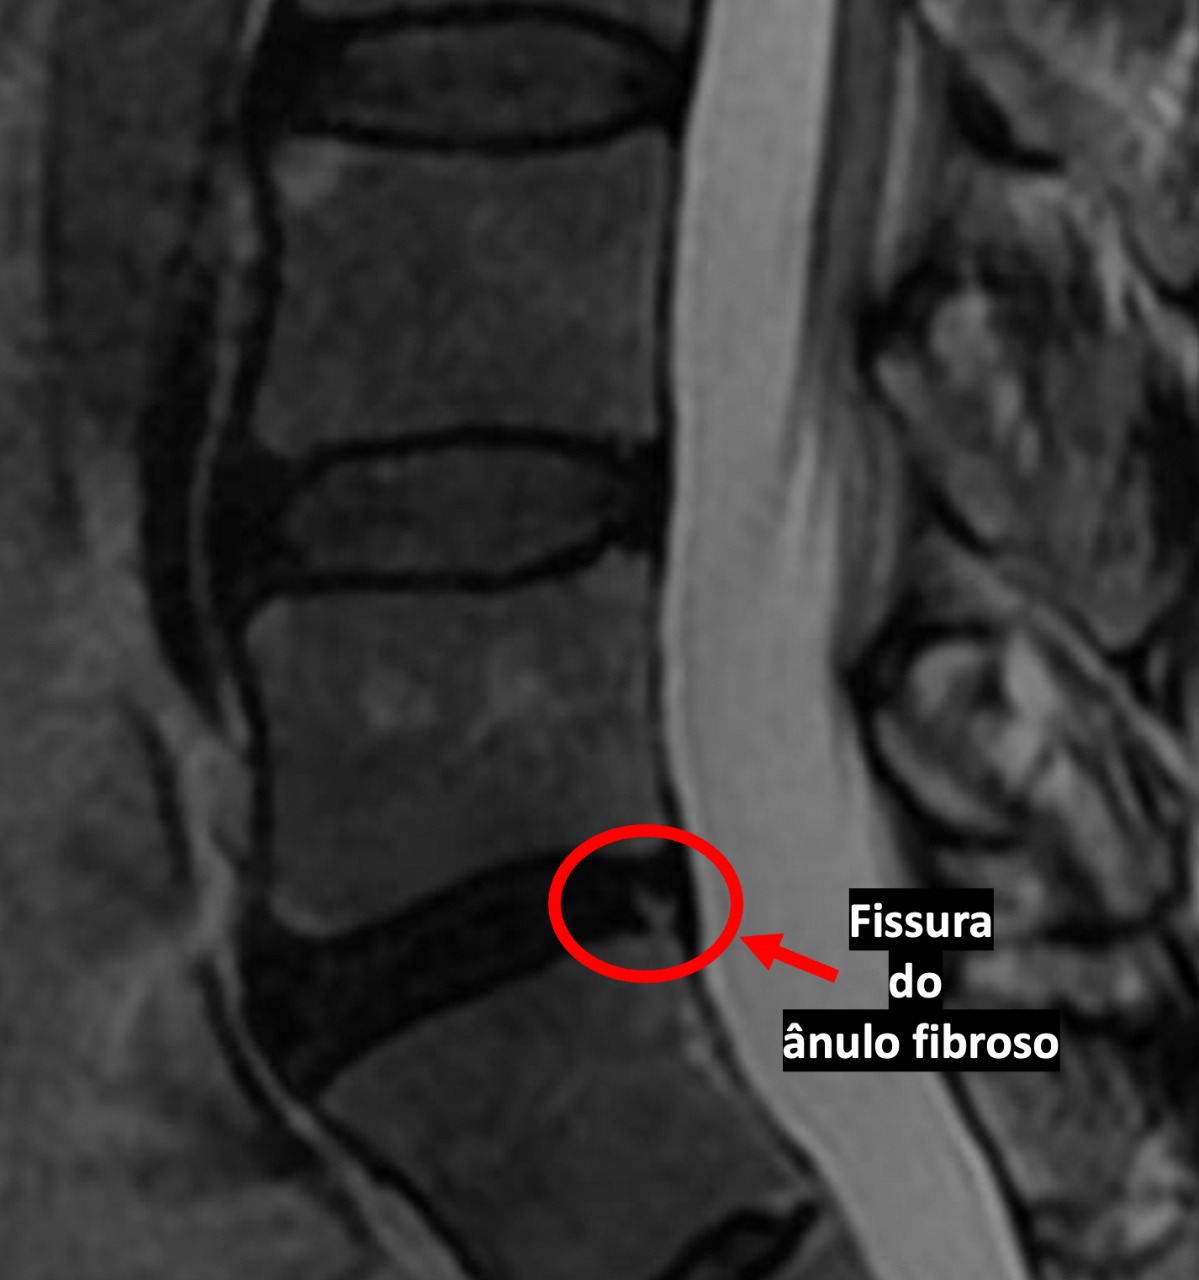

Olá boa noite Dr. na minha ressonância deu Hérnia discal centro látero foraminal em l4 l5 e também tem rotura do ânulo fibroso do tipo radial. isso é mto grave de ? mto obrigado

Olá Rita! A fissura do ânulo fibroso só é sintomática na fase aguda da lesão. Normalmente em 4 a 6 semanas de tratamento o sintoma melhora e as atividades esportivas podem ser retomadas. É importante fazer uma avaliação com seu médico de confiança para avaliar em que fase está seu problema. Obrigado pela pergunta

Olá, boa tarde! Doutor, eu tenho esse problema de fissura no ânulo fibroso em L5-S1.

Nessa condição, posso engravidar? Ou é melhor esperar uma melhora com os exercícios?